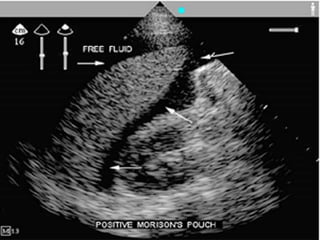

Imaging – Ultrasound

• Quick

• Can be performed at bedside

• FAST: Focused Assessment with

Sonography for Trauma

• Rapid examination to identify free

intraperitoneal fluid and/or pericardial

fluid

Imaging – Ultrasound • Quick • Can be performed at bedside • FAST: Focused Assessment with Sonography for Trauma • Rapid examination to identify free intraperitoneal fluid and/or pericardial fluid